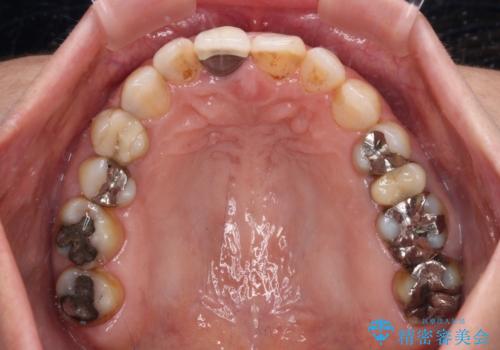

- 上下前歯のデコボコと、治療途中の歯を気にして来院された患者様です。

根管治療が必要な歯は事前に処置を行った上で矯正治療を開始し、概ね歯列が整ったところでセラミッククラウンなどに置き換え、その後インビザラインを1セット使用して仕上げていくこととしました。

痛みがなくなり歯列が整ったことで、残っている銀歯も気になり始めているようです。

マウスピース生活に疲れてしまったとのことで、暫くお休みをしてから銀歯の治療を再開していく予定です。